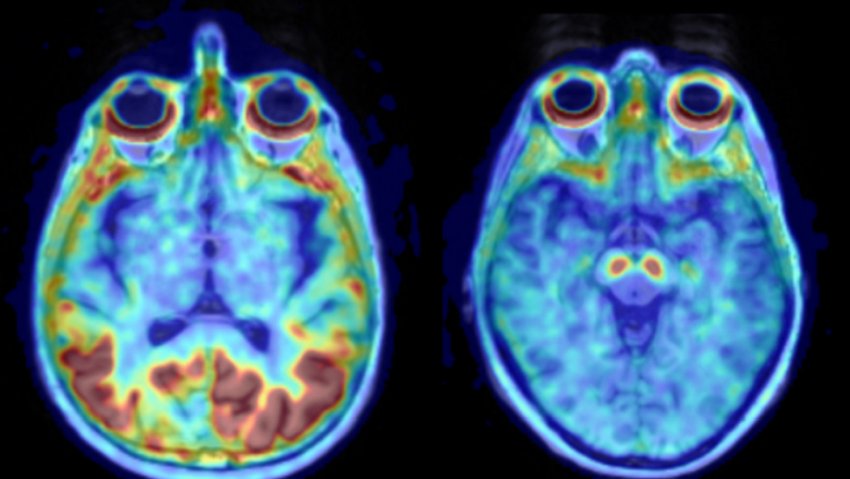

Assorbimento di tau patologica (sinistra) e un cervello sano (destra). Fonte: Ruben Smith

La prima proteina ad aggregarsi nel MA è l'Aβ. Uomini e donne sono influenzati ugualmente dalle prime fasi della malattia e l'analisi non ha mostrato differenze nell'accumulo di Aβ. La disfunzione della memoria sorge più tardi, quando la tau inizia ad accumularsi. Sono di più donne che uomini ad essere colpite da problemi di memoria dovuta al MA, e i ricercatori hanno dimostrato che è la tau ad avere un tasso di accumulo più elevato nelle donne.

"I tassi di accumulo di tau variano notevolmente tra gli individui dello stesso sesso, ma nel lobo temporale, che è interessato al MA, abbiamo trovato un tasso di accumulo più alto del 75% nelle donne come gruppo, rispetto agli uomini", spiega Ruben Smith, primo autore dello studio.